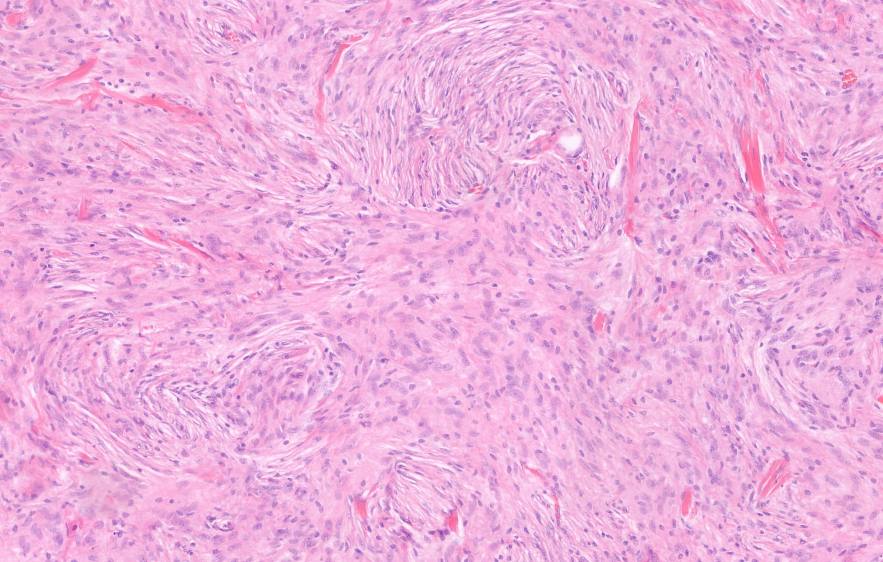

Neuropathology comprises the histopathological diagnosis of lesions of the central and peripheral nervous system as well as skeletal muscle. We offer detailed classification of central nervous system tumors and inflammatory and degenerative diseases, incorporating immunohistochemical and molecular markers. Our findings provide an essential basis for neurosurgical and neuro-oncological treatment decisions.